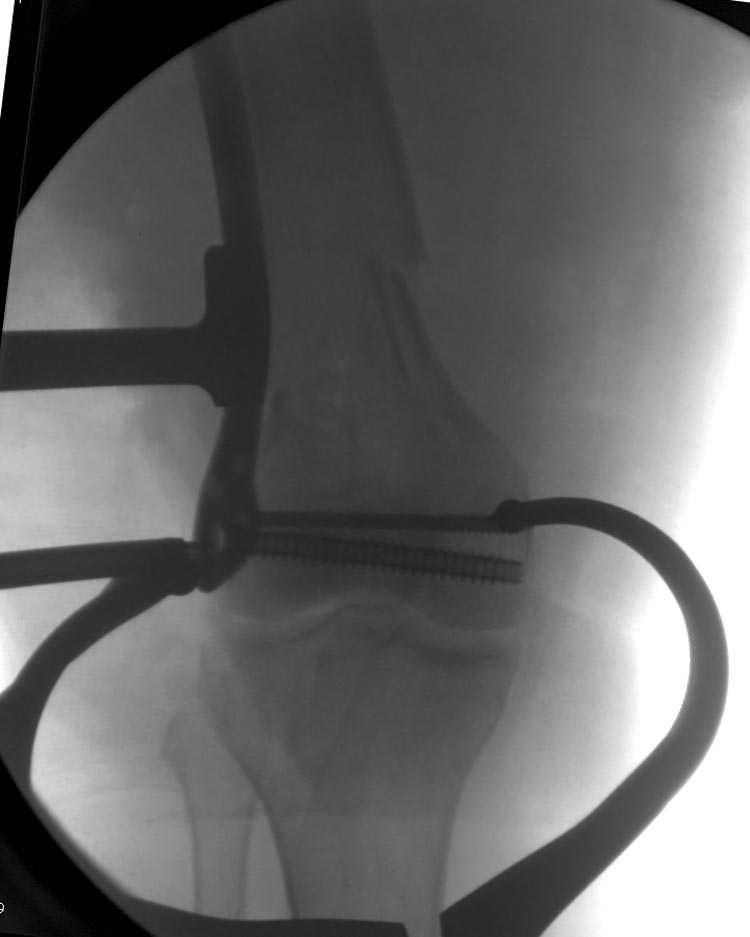

[Ortho] Дистальный перелом бедра

Бесспорно, предлагаемый ретроградный метод имеет свои преимущества, но имеется опасность при манипуляции интрамедуллярным гвоздем расколоть мыщелки.

Раскол можно предупредить шурупами, но короткий дистальный фрагмент навряд ли позволит добиться адекватной стабильности конструкции. Стандартные гвозди не рассчитаны для таких переломов, и если все таки желаете провести фиксацию гвоздем, тогда надо заказывать специальный custom made nail т.е. с расширенной возможностью дистальной блокировки.

Поэтому такие меж и над- мыщелковые переломы более предпочтительным считается фиксировать мыщелковыми пластинами

Устанавливается из малого разреза "не вскрывая сустав" со стороны латерального мыщелка, и Insertion Jig позволяет установить пластину "мостовидно" перкутанно в проксимальном отделе, "не вскрывая и не трогая" место перелома.

Имя     : distal femur crm 1.jpg